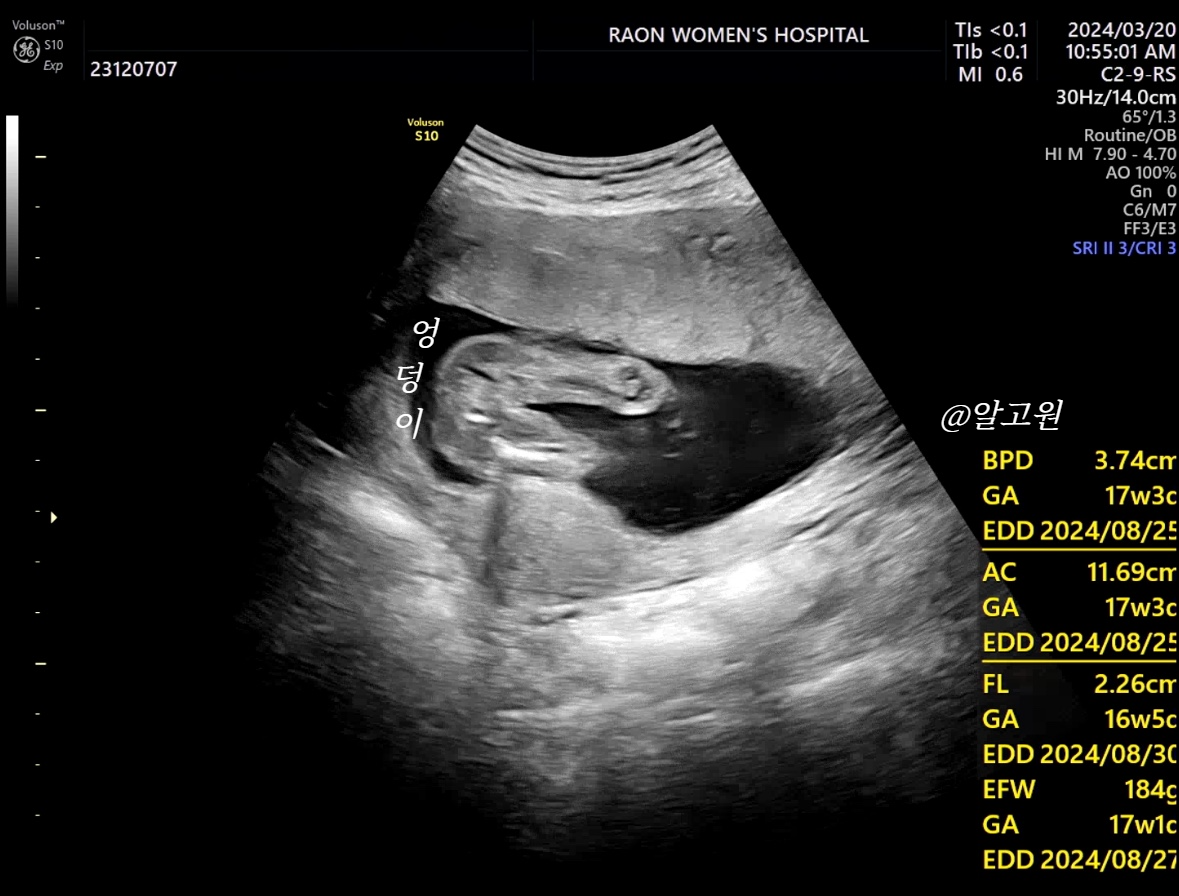

3. 성별 확인

-아래는 엉덩이부터 다리 초음파 인데요.

이걸로 보통 판단하시는 듯 해요!

저희 아가는 딸 확정!!!👏👏👏